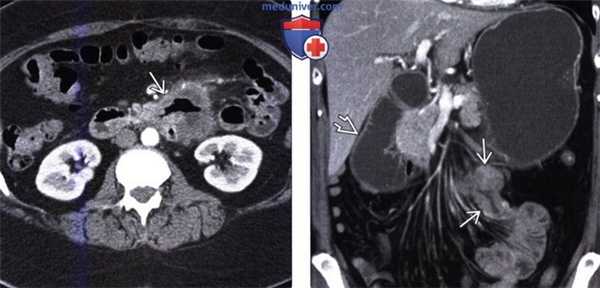

(б) Фотография макропрепарата: три полиповидных новообразования с центральным изъязвлением. Метастазы в тонкой кишке у мужчины 63 лет, которому год тому назад выполнена правосторонняя гемиколэктомия по поводу рака ободочной кишки.

При КТ в коронарной проекции визуализируется поражающая брюшину опухоль (стрелка), сдавливающая петлю тонкой кишки и вызывающая непроходимость.

Отмечаются наполненные жидкостью расширенные петли тонкой кишки и «симптом фекалий в тонкой кишке» (звездочка).

На пораженной брюшине выявляются множественные узелки (указатели).

Среди органов желудочно-кишечного тракта метастазы чаще всего встречаются в тонкой кишке. Первичные опухоли ободочной кишки, поджелудочной железы, желудка и яичников могут распространятся на тонкую кишку путем прямой инвазии или по брюшине. В тонкую кишку гематогенным путем могут метастазировать рак молочной железы, рак легких и меланома.

Метастазы в тонкой кишке могут приводить к непроходимости, перфорации, завороту и кишечному кровотечению. К типичным макроскопическим признакам можно отнести множественность поражения, доминирование экстрамурального компонента и подслизистое и субсерозное прорастание опухоли. При поражении тонкой кишки путем распространения по брюшине отмечается утолщение кишечной стенки, инфильтрация брыжеечной жировой клетчатки и патологическое утолщение большого сальника.